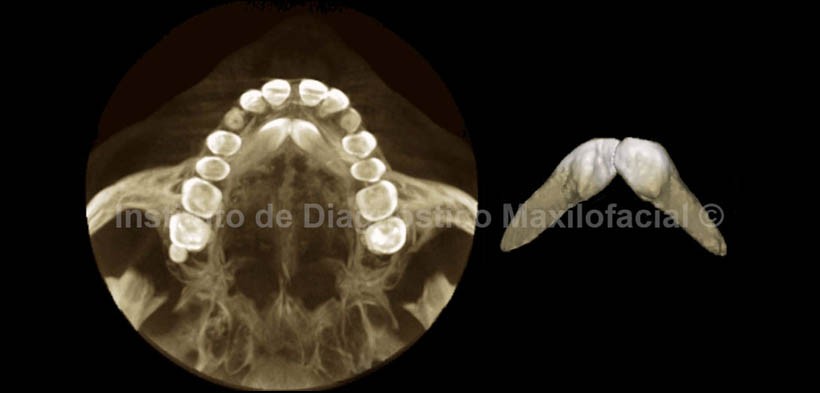

En las imagenes tridimensionales (Fig. 5 y Fig. 6) se observan las piezas en mención libres de tejido óseo, así como el aislamiento de la pieza 1.8 y la mencionada alteración de tamaño. En la vista axial 3D, se muestra la convergencia de las piezas en sentido póstero anterior y el contacto entre si a nivel coronal.